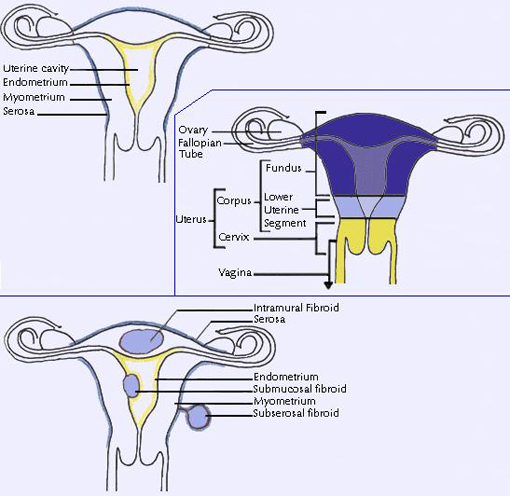

leiomyoma fibroid uterine uterus types fibroids ppt location primary three there leiomyomas powerpoint presentation multiple classified primarily according most slideserve

uterine fibroids bleeding leiomyoma leiomyosarcoma fibroid abnormal endometrial intramural submucosal subserosal pedunculated malignancy cervical hyperplasia sarcomas lecturio

leiomyomas uterine clinical review location radiology key